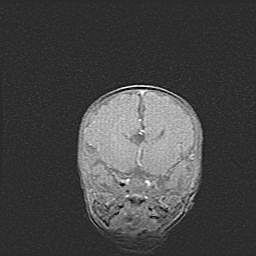

Открытая гидроцефалия.

Возраст: 9 месяцев 12 дней

Вес: 6800 г

Пол: мужской

Окружность головы: 41,5 см

Срок гестации: 28 недель

Гидроцефалия головного мозга у новорожденных имеет характерный признак: опережающий рост окружности головы приводит к визуально хорошо определяемой гидроцефальной форме сильно увеличенного в объёме черепа. Детские неврологи определяют следующие симптомы гидроцефалии у грудничков: выбухающий напряжённый родничок, частое запрокидывание головы, смещение глазных яблок к низу.